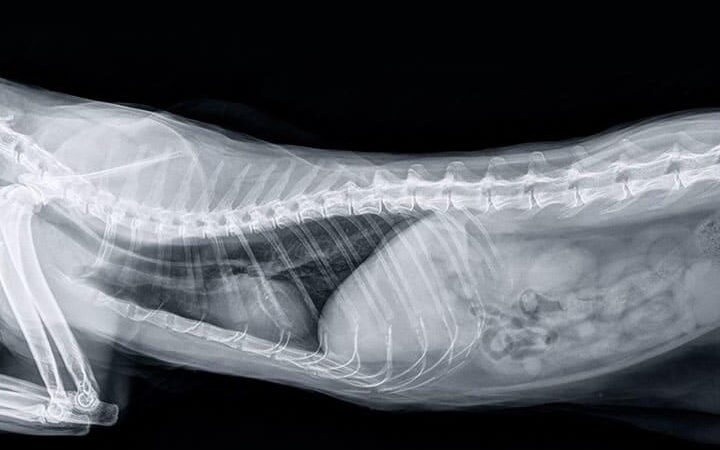

- レントゲン検査: 腸閉塞など構造的な問題を特定します。